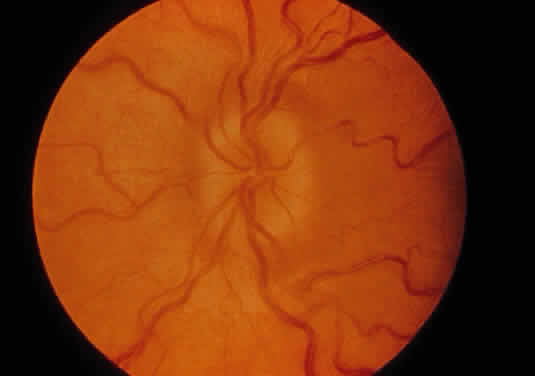

Progressive diffuse punctate stromal corneal opacities occur in all patients. They may conceal retinal degeneration and result in progressive visual loss.14,15 When the retina can be evaluated, a retinitis pigmentosa-like picture indistinguishable from other forms of heredofamilial retinal pigmentary dystrophies usually is present. The electroretinogram is diminished or nonrecordable.16 Glaucoma is relatively rare17 but has been reported in some patients.14,18 Optic nerve head swelling and optic atrophy are common10 (Fig. 2). Congenital cataracts occasionally have been observed.19

Fig. 2. Optic nerve head and peripapillary elevation in a patient with Hurler syndrome (MPS I-H).